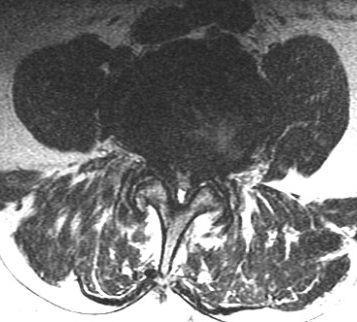

Halswirbelsäule

Zumeist ist eine Kernspintomographie ausreichend. Bei Verdacht auf Rückenmarksschaden ist zusätzlich eine elektrophysiologische Untersuchung der Nervenleitung erforderlich.